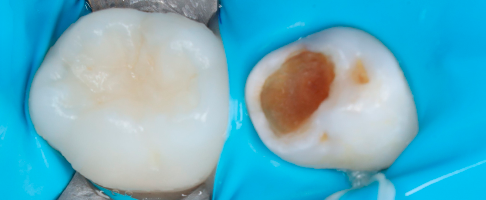

Лечение кариеса постоянных зубов

Лечение кариеса системой ICON